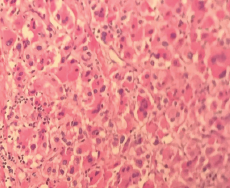

Imágenes y Cirugía

Natalia González Alcolea, María Dolores Chaparro Cabezas, Félix Martínez Arrieta, Victor Sánchez Turrión